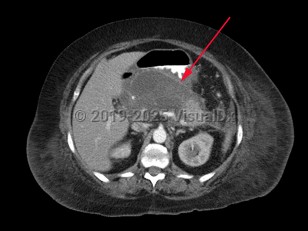

Pancreatic pseudocyst

A pancreatic pseudocyst is a localized, mature, fluid-filled collection, sometimes with debris, located outside of the pancreas. It has a nonepithelialized wall of fibrous and granulation tissue, with no necrosis present. Pancreatic pseudocysts typically appear at least 4 weeks after an episode of acute pancreatitis or blunt or penetrating pancreatic trauma. Pancreatic pseudocysts can also form in patients with chronic pancreatitis if there is an acute exacerbation of the underlying pancreatitis. Ten percent of patients with chronic pancreatitis will develop pseudocysts. Pancreatic pseudocysts are more commonly diagnosed in males.

Most cases of pancreatic pseudocyst resolve without intervention, but they may produce a wide range of signs, symptoms, and clinical manifestations. These may include abdominal mass, abdominal pain, fever, chills, and jaundice.